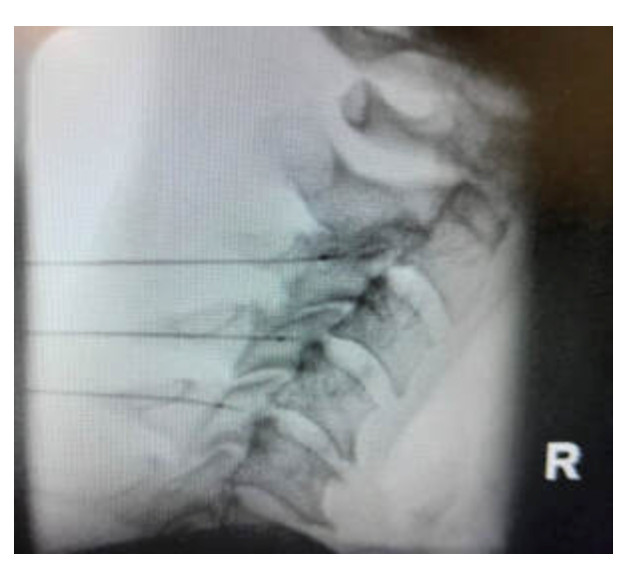

Hydrodilatation is a simple, minimally invasive treatment for frozen shoulder. It’s usually done in a clinic with a needle, although in more complex cases, it may be done in a special treatment room with X-ray guidance. The goal is to inject fluid into the shoulder joint to stretch the thickened joint capsule, help reduce inflammation and improve movement, and it can be done at any stage of the condition. This procedure is very effective. Most people see a big improvement in their shoulder's range of motion after just one injection. It not only helps with movement but also relieves pain, which is important because pain can make it harder to stretch the joint and improve mobility. Recovery is usually quick, and most patients can return to normal activities the same day. It's also recommended to do stretching exercises to help with recovery. Hydrodilatation is generally safe when done by experienced specialists, but it’s important to talk to your doctor about the benefits, risks, and other options before deciding if it’s right for you.